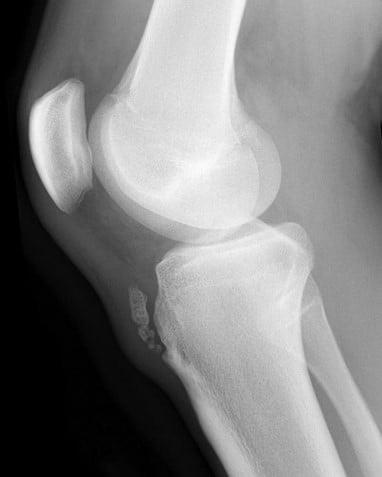

Osgood-Schlatter Disease

Case courtesy of Assoc Prof Frank Gaillard, Radiopaedia.org From the case rID: 7511